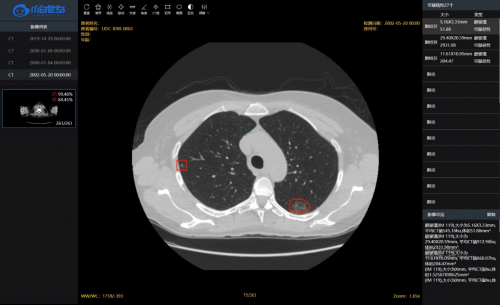

该 CT影像诊断系统,实现新冠肺炎CT影像诊断可在20秒内完成对一份病历的分析,并且在回顾性测试病历上准确率和召回率均达95%以上。为鉴别新冠肺炎与普通肺炎,该模型评估指标AUC值为0.97,外加额外的临床特征,AUC值可达0.98,大幅提升影像诊断的精准性与便捷性。

此次抗击疫情,DenseNet模型在新冠肺炎影像识别中,发挥出巨大作用。根据DenseNet的深度学习算法,计算机预先学习训练数据,学习新冠肺炎的特征,在为患者诊断的过程中,计算机自动读取CT影像,利用该算法自动分析、对比,查找出与新冠肺炎相匹配的特征,从而达到快速、精准的诊断效果。目前,该系统相关成果已经整理成学术论文,投稿至医学领域顶级期刊。